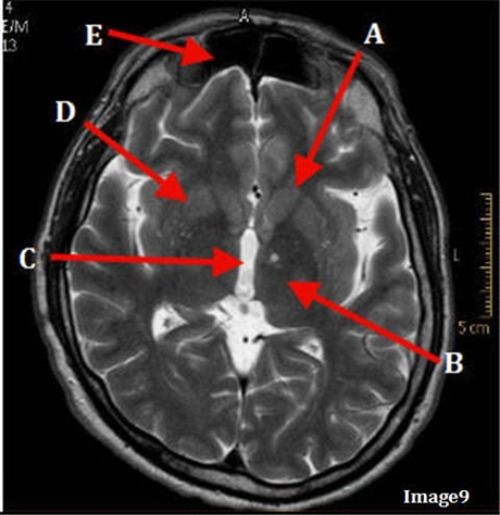

Letter A in image 14 is pointing to:

D. Pituitary gland

Letter F in image 14 is pointing to:

D. Internal carotid artery

Letter E in Image 14 is pointing to:

E. Fornix

Letter D in Image 14 is pointing to:

D. Sagittal sinus

Letter B in Image 14 is pointing to:

C. Lateral ventricle

Letter C in Image 14 is pointing to:

A. Corpus callosum